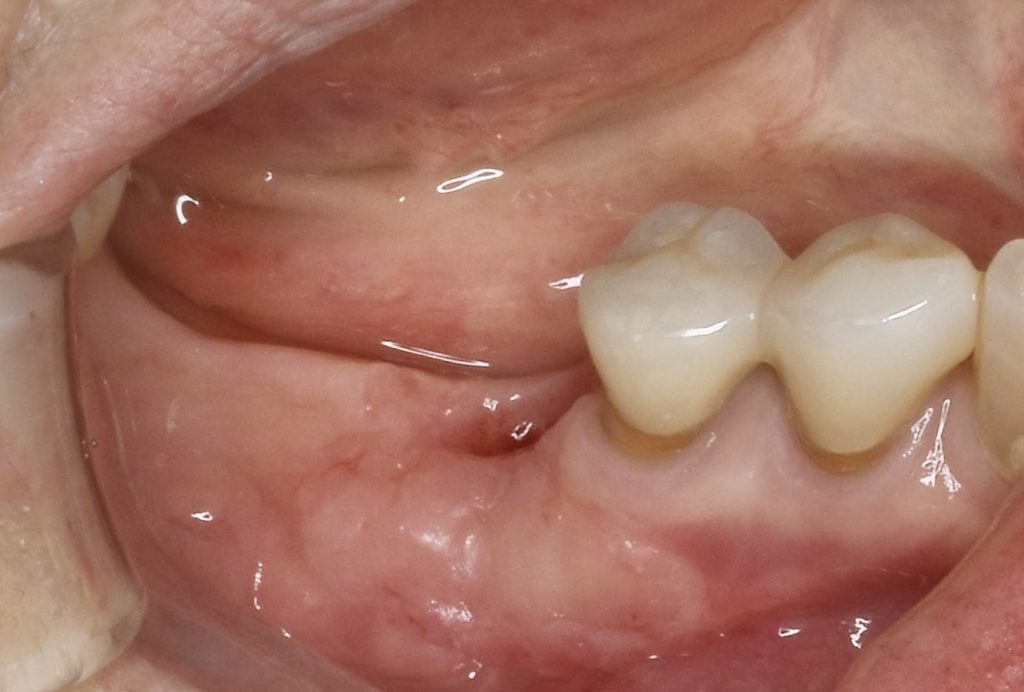

下記の症例はインプラントだけ埋入すれば良いわけではありません。

周囲環境を整え長期的に安定し、長持ちさせるインプラントを目指す必要があります。

その為に歯肉を移植しインプラント周囲に強い抵抗力を持つ歯肉を作る事が大切です。

遊離歯肉移植術にかかる費用 約121000円(税込)